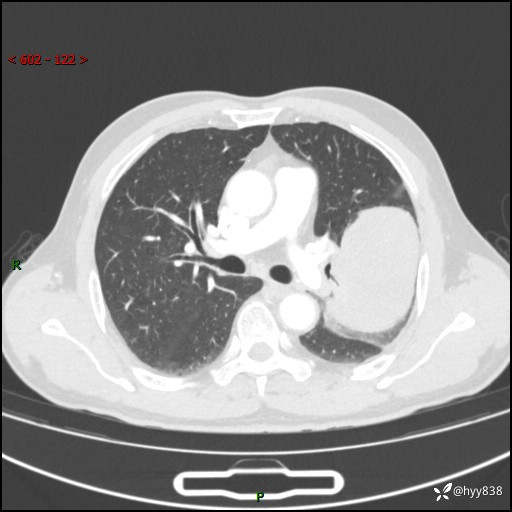

68岁/男,发现左下肺占位5天。如此大的肿块,患者竟然没有症状---结果公布~

【患者信息】:68岁/男

【主诉】:检查发现左下肺占位5天。

【现病史及既往史】:患者于4天前外院行“经尿道钬激光碎石术”,住院期间胸部CT检查发现左下肺肿块,患者平素无明显咳嗽咳痰,无心慌、胸闷、胸痛、呼吸困难、低热、盗汗,无头痛、头晕,无腹痛、腹胀等不适,现患者为求进一步治疗,遂来我院就诊,以“左下肺肿块”收入我科。 患者自起病以来,精神可,睡眠可,饮食可,大小便正常,体重无明显改变。

【检查】:胸部CT增强扫描